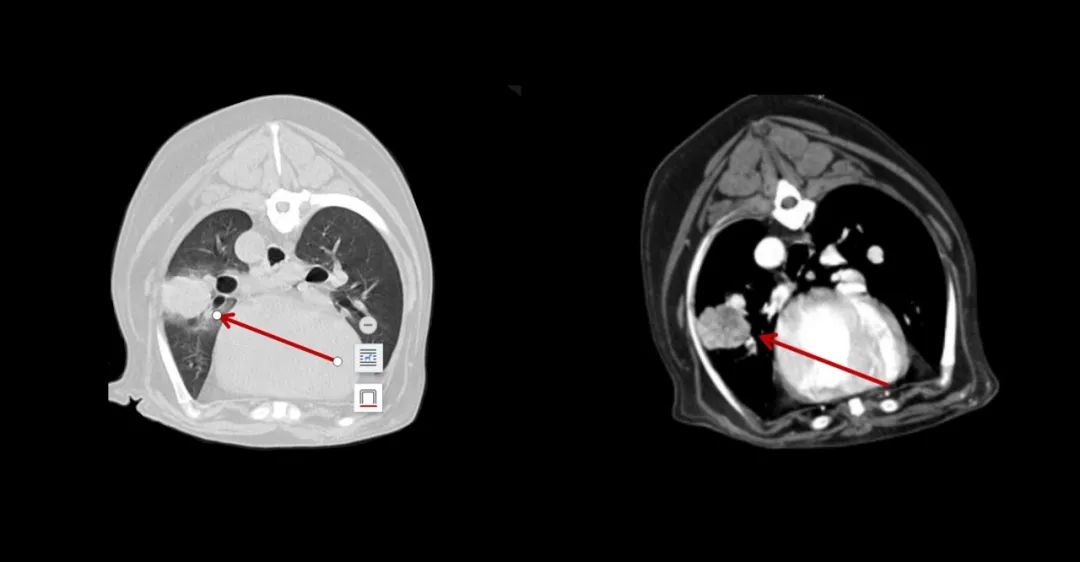

▲7歲成年犬,乳腺癌術(shù)后1年,發(fā)現(xiàn)肺部轉(zhuǎn)移。

▲小白兔,白又白,兩只耳朵豎起來~這個小家伙也不幸中招,得了肝癌。